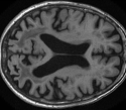

Looking at sample synthetic PET images in Fig. 3, it can be seen that all of the models are able to make reasonable predictions. The outputs of the U-PET and U-PET (no att.) look very similar and are smoothed compared to the input. The pix2pix predicts more details, which seem to be important for the discriminator. However, even though this model has finer predictions, the intensity values are worse compared to the U-PET and U-PET (no att.) as seen in Fig. 2; an example is given in Fig. 3 in the second row.

From a clinical perspective, the synthetic generated PET show a smoother version of the real PET images but keep the same pattern of FDG uptake, especially, hypometabolism in the respective brain areas. This backs up our hypothesis, that MRI contains information that correlates with the functional information of PET images. Moreover, the synthetic PET could be used as complementary visualization for physicians beyond the task of classification.